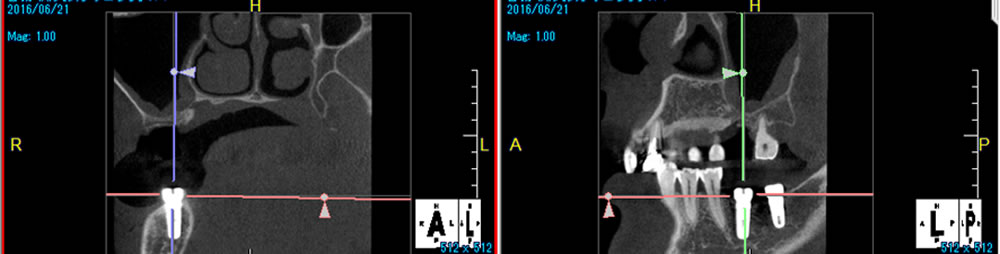

CTでの精密検査/ステント試摘

(図:術前CT・ステント試摘)

リスクを最小限に抑え、よりスムーズな手術を実現するため、CT精密検査でインプラント埋入時に使用するステントの位置を確認しました。